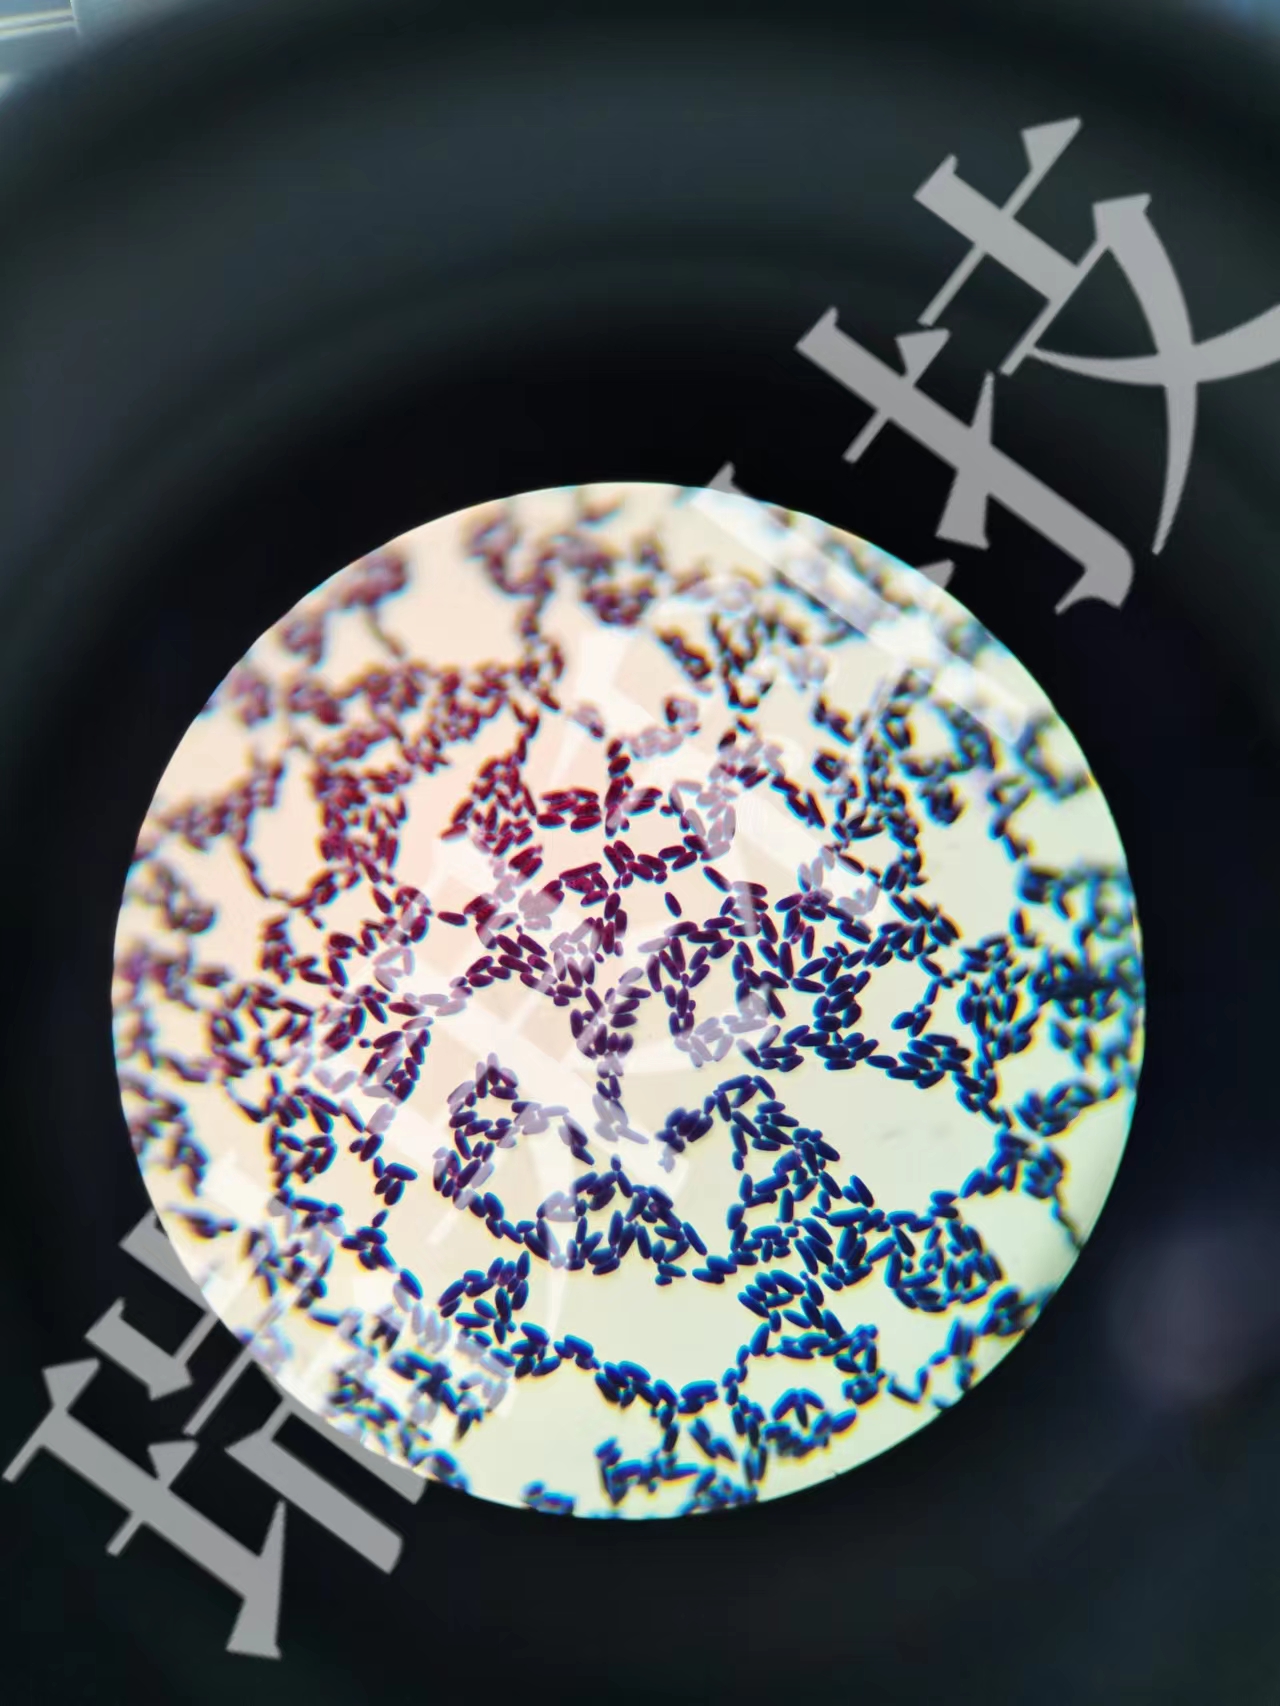

白介素-1(Interleukin-1, IL-1)并非一個單一的分子,而是一個龐大的家族,其中最核心的成員是IL-1αIL-1β。這兩種細胞因子是機體抵御病原體入侵和組織損傷的“急先鋒”,它們在炎癥和免疫反應(yīng)中扮演著至關(guān)重要的角色,堪稱免疫系統(tǒng)的“總指揮”之一。

IL-1主要由巨噬細胞、單核細胞、樹突狀細胞等先天免疫細胞分泌。當(dāng)這些細胞感受到來自細菌、病毒、或組織損傷釋放的危險信號(如病原體相關(guān)分子模式PAMPs或損傷相關(guān)分子模式DAMPs)時,IL-1的合成和釋放就會被迅速觸發(fā)。